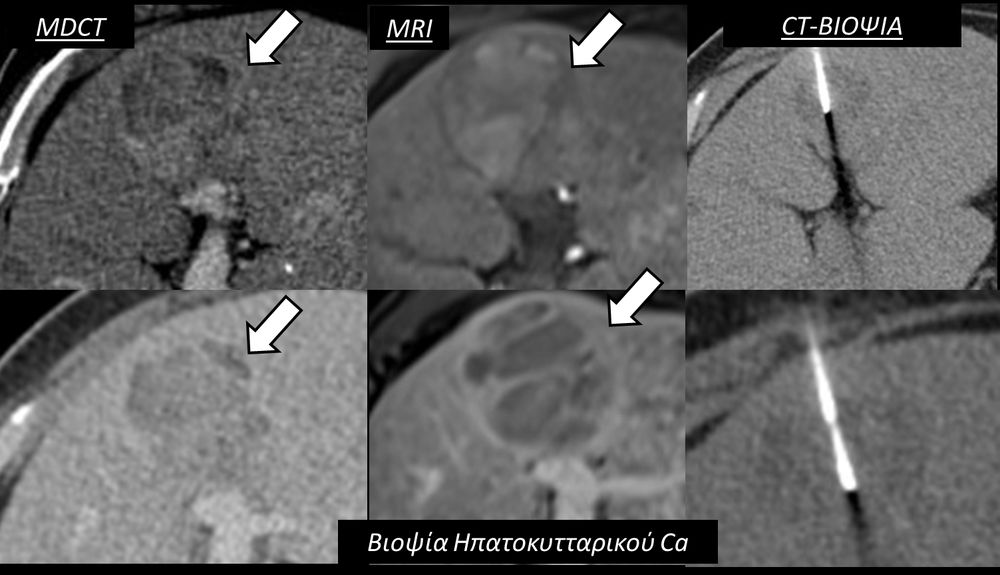

Η διαδερμική βιοψία είναι μία ελάχιστα επεμβατική μέθοδος λήψης υλικού από τον όγκο για κυτταρολογική και ιστολογική εξέταση, από εστιακές αλλοιώσεις του ήπατος, πνεύμονα, νεφρού κλπ. Συστήνεται από τον κλινικό ιατρό ανάλογα με το είδος και το μέγεθος της βλάβης και πραγματοποιείται με ασφάλεια από επεμβατικό ακτινολόγο με την καθοδήγηση αξονικού τομογράφου ή υπερήχων. Στη σύγχρονη ογκολογική θεραπεία όπου γίνεται προσπάθεια καταπολέμησης του καρκίνου σε μοριακό επίπεδο κρίνεται αναγκαία η ακριβής ιστολογική ταυτοποίηση του όγκου ώστε να εφαρμοσθεί εξατομικευμένη θεραπεία για το βέλτιστο αποτέλεσμα. Οι κατευθυνόμενες βιοψίες στοχευουν στο να παρέχουν στον κλινικό ογκολόγο το απαραίτο ιστοπαθολογικό υλικό που θα του επιτρέψει να εφαρμόσει την κατάλληλη θεραπεία για τον ογκολογικό ασθενή.